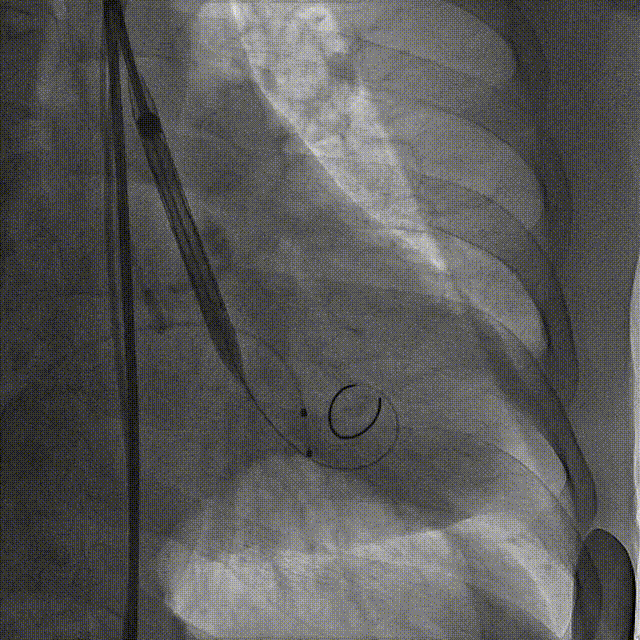

4.TaurusElite AV23号瓣膜定位及释放。瓣膜初始定位0位,开花后120次起搏,释放到工作位后造影显示锚定充足,位置良好,冠脉未见遮挡,继续缓慢旋转手柄,轻推输送器,瓣膜逐一脱钩,顺利释放。

瓣膜初始定位

瓣膜释放过程

工作位造影

瓣膜脱钩